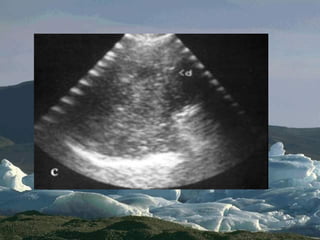

A lines = default normal

 Horizontal echo

reflection at exact

multiples of intervals

from surface to

bright reflector.

 Dry lung OR PNTX

 Decay with depth

 Obliterated by B

pleura A

A lines =default normal  Horizontal echo reflection at exact multiples of intervals from surface to bright reflector.  Dry lung OR PNTX  Decay with depth  Obliterated by B pleura A A A A A A